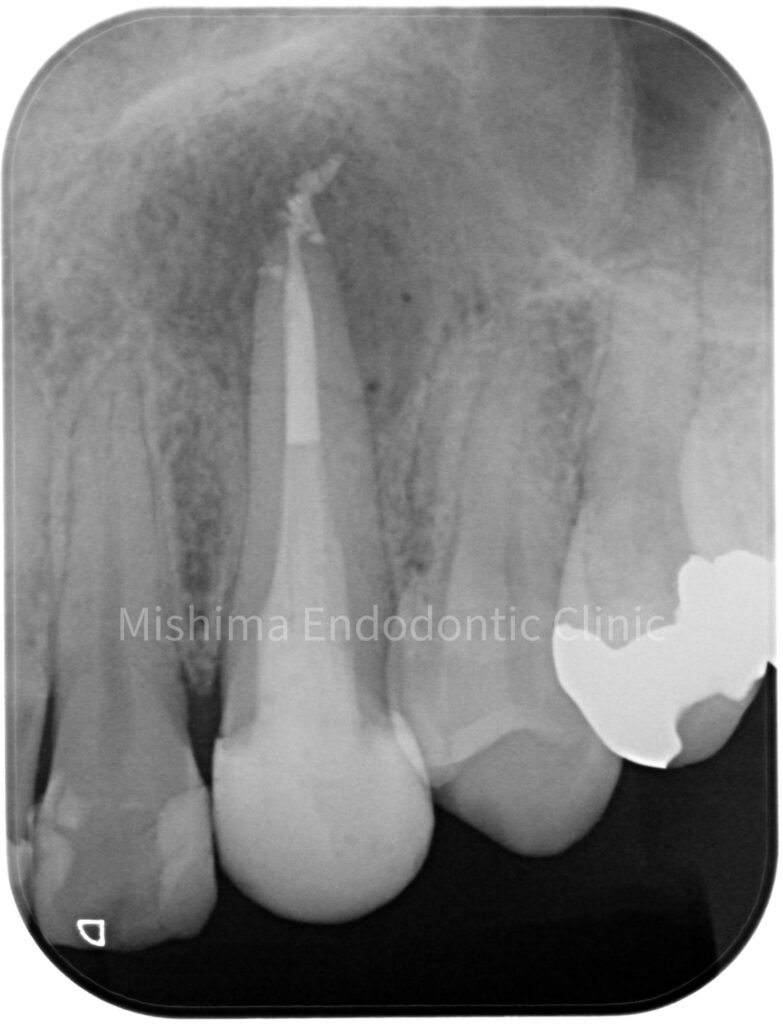

Before

| 治療内容 | 23が既に根管治療が介入され仮封の状態で、サイナストラクト、自発痛を認めた。 根管治療を行うも症状の改善認めず、歯根端切除術へ移行。 |

術前

根管治療 直後

歯根端切除術 直後